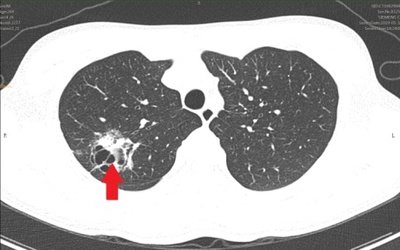

常规的肺部检查,多以胸部X光,也就是我们常说的胸片为主,但是胸透、X光片对肺癌的敏感性非常低,有局限性,正位胸片上,肺组织与纵膈、心脏及膈肌有重叠,且空间的分辨率非常差,难以做到早期发现,只能发现比较大的肿瘤,此时很多已经是中晚期了。与之相比,螺旋CT则可通过高速、连续的数据采集,且为横断面断层成像,可以发现位于解剖学死角或胸片因组织结构重叠等原因造成的病灶遗漏,明显提高了肺内小结节病变的检出能力,对早期发现肺癌具有重大意义。

据国家肺癌筛查研究表明,低剂量螺旋CT是对肺部筛查有助于发现早期肺癌,特别是周围型非小细胞肺癌,其诊出率约为胸片的10倍。可发现肺部1mm的结节,是早期肺癌诊断的“金标准”.低剂量螺旋CT扫描,获得图像质量和常规剂量扫描差异不大,且患者所接受辐射剂量降低90%.

低剂量螺旋CT是肺癌普查的首选准确方法